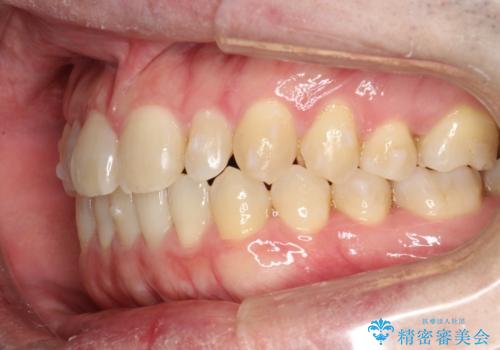

前歯の隙間 インビザラインにて整った歯並びへ

- 前歯の隙間が気になるとのことで来院されました。

インビザラインにて矯正治療を行うこととしました。

下の歯と歯の間にわずかに隙間をつくり、上の前歯の隙間を閉じました。